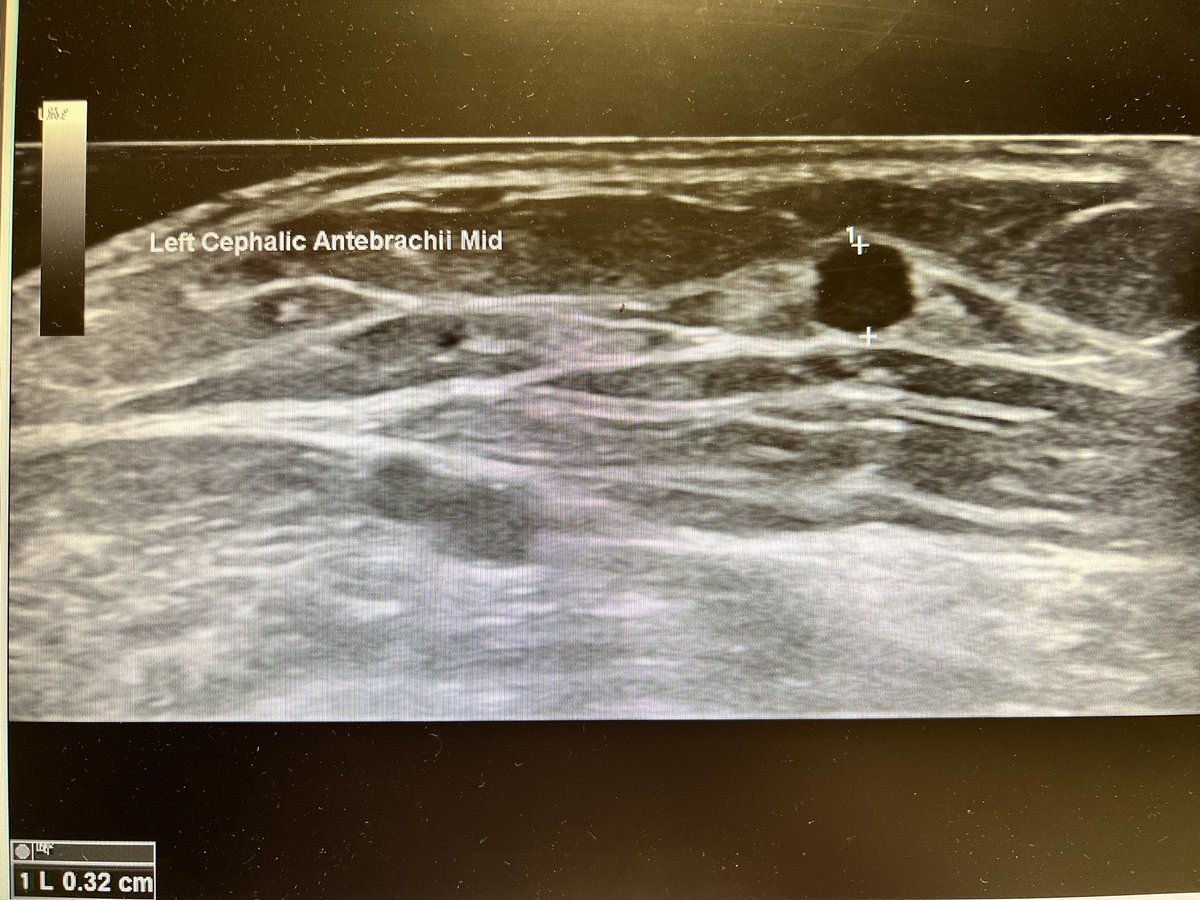

Brachial artery and mid level forearm cephalic vein before (fig 1-2) and exactly 2 days!!!! after (fig 3-4) the creation of a

#VasQ#RCAVF in a#CKD patient@wasse_m@jimbog_76@OBaumgaertner_#VascularAccessCenter#Hamburg#Barmbek#LaminateMedicalpic.twitter.com/0aX0710Wnu